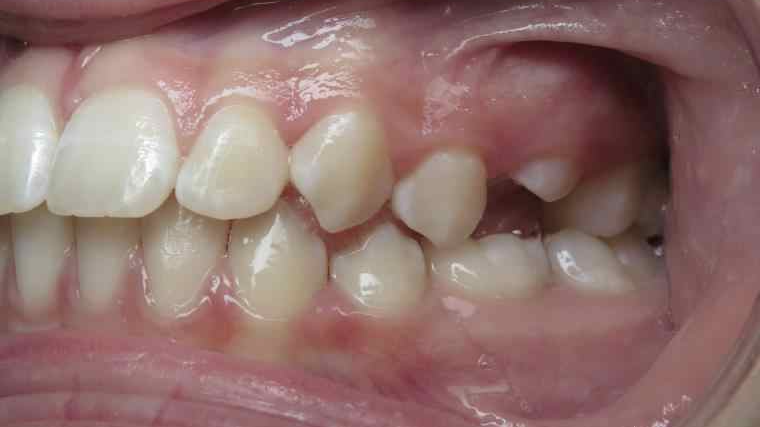

inversion postérieur coté droit et espace entre les dents du haut et du bas (diastèmes)

appareillage mobile pendant 35 mois

surveillance évolution de la dentition pendant 5 ans